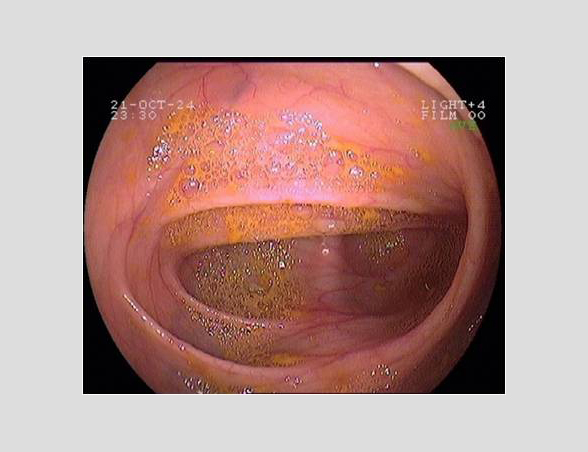

Imágenes tomadas durante la endoscopia digestiva alta y la colonoscopia. Se aprecia una mucosa de aspecto y vascularización normal, sin lesiones visibles. Se progresa con el colonoscopio hasta el íleon. Todo resulta macroscópicamente normal. Se toman biopsias de todos los segmentos explorados.

La endoscopia es el método de elección para el diagnóstico y seguimiento de la EII. Permite una visión macroscópica de la mucosa intestinal y la toma de múltiples biopsias para el estudio histológico.

Realizamos una endoscopia digestiva alta y una colonoscopia a la paciente con toma de biopsias, obteniendo el informe de Anatomía patológica.